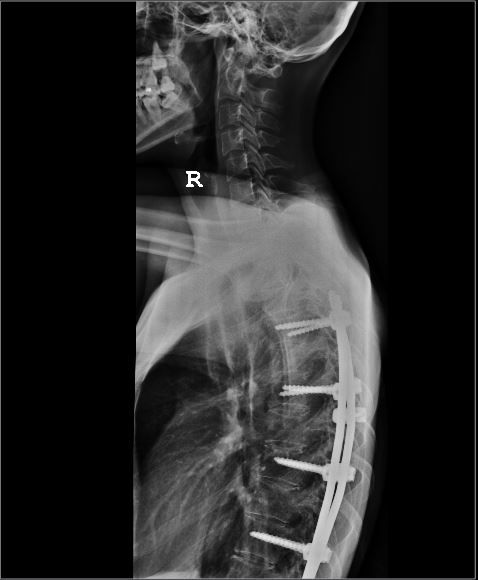

This is the implant inside my body. My spine was originally a ‘S’ shape spine.

It is not entirely straight now as you can see from the Xray..

The chiropractor also told me that I am actually putting additional stress on the other parts of the spine. 🙁 This is probably why my neck and head is always aching. sigh..